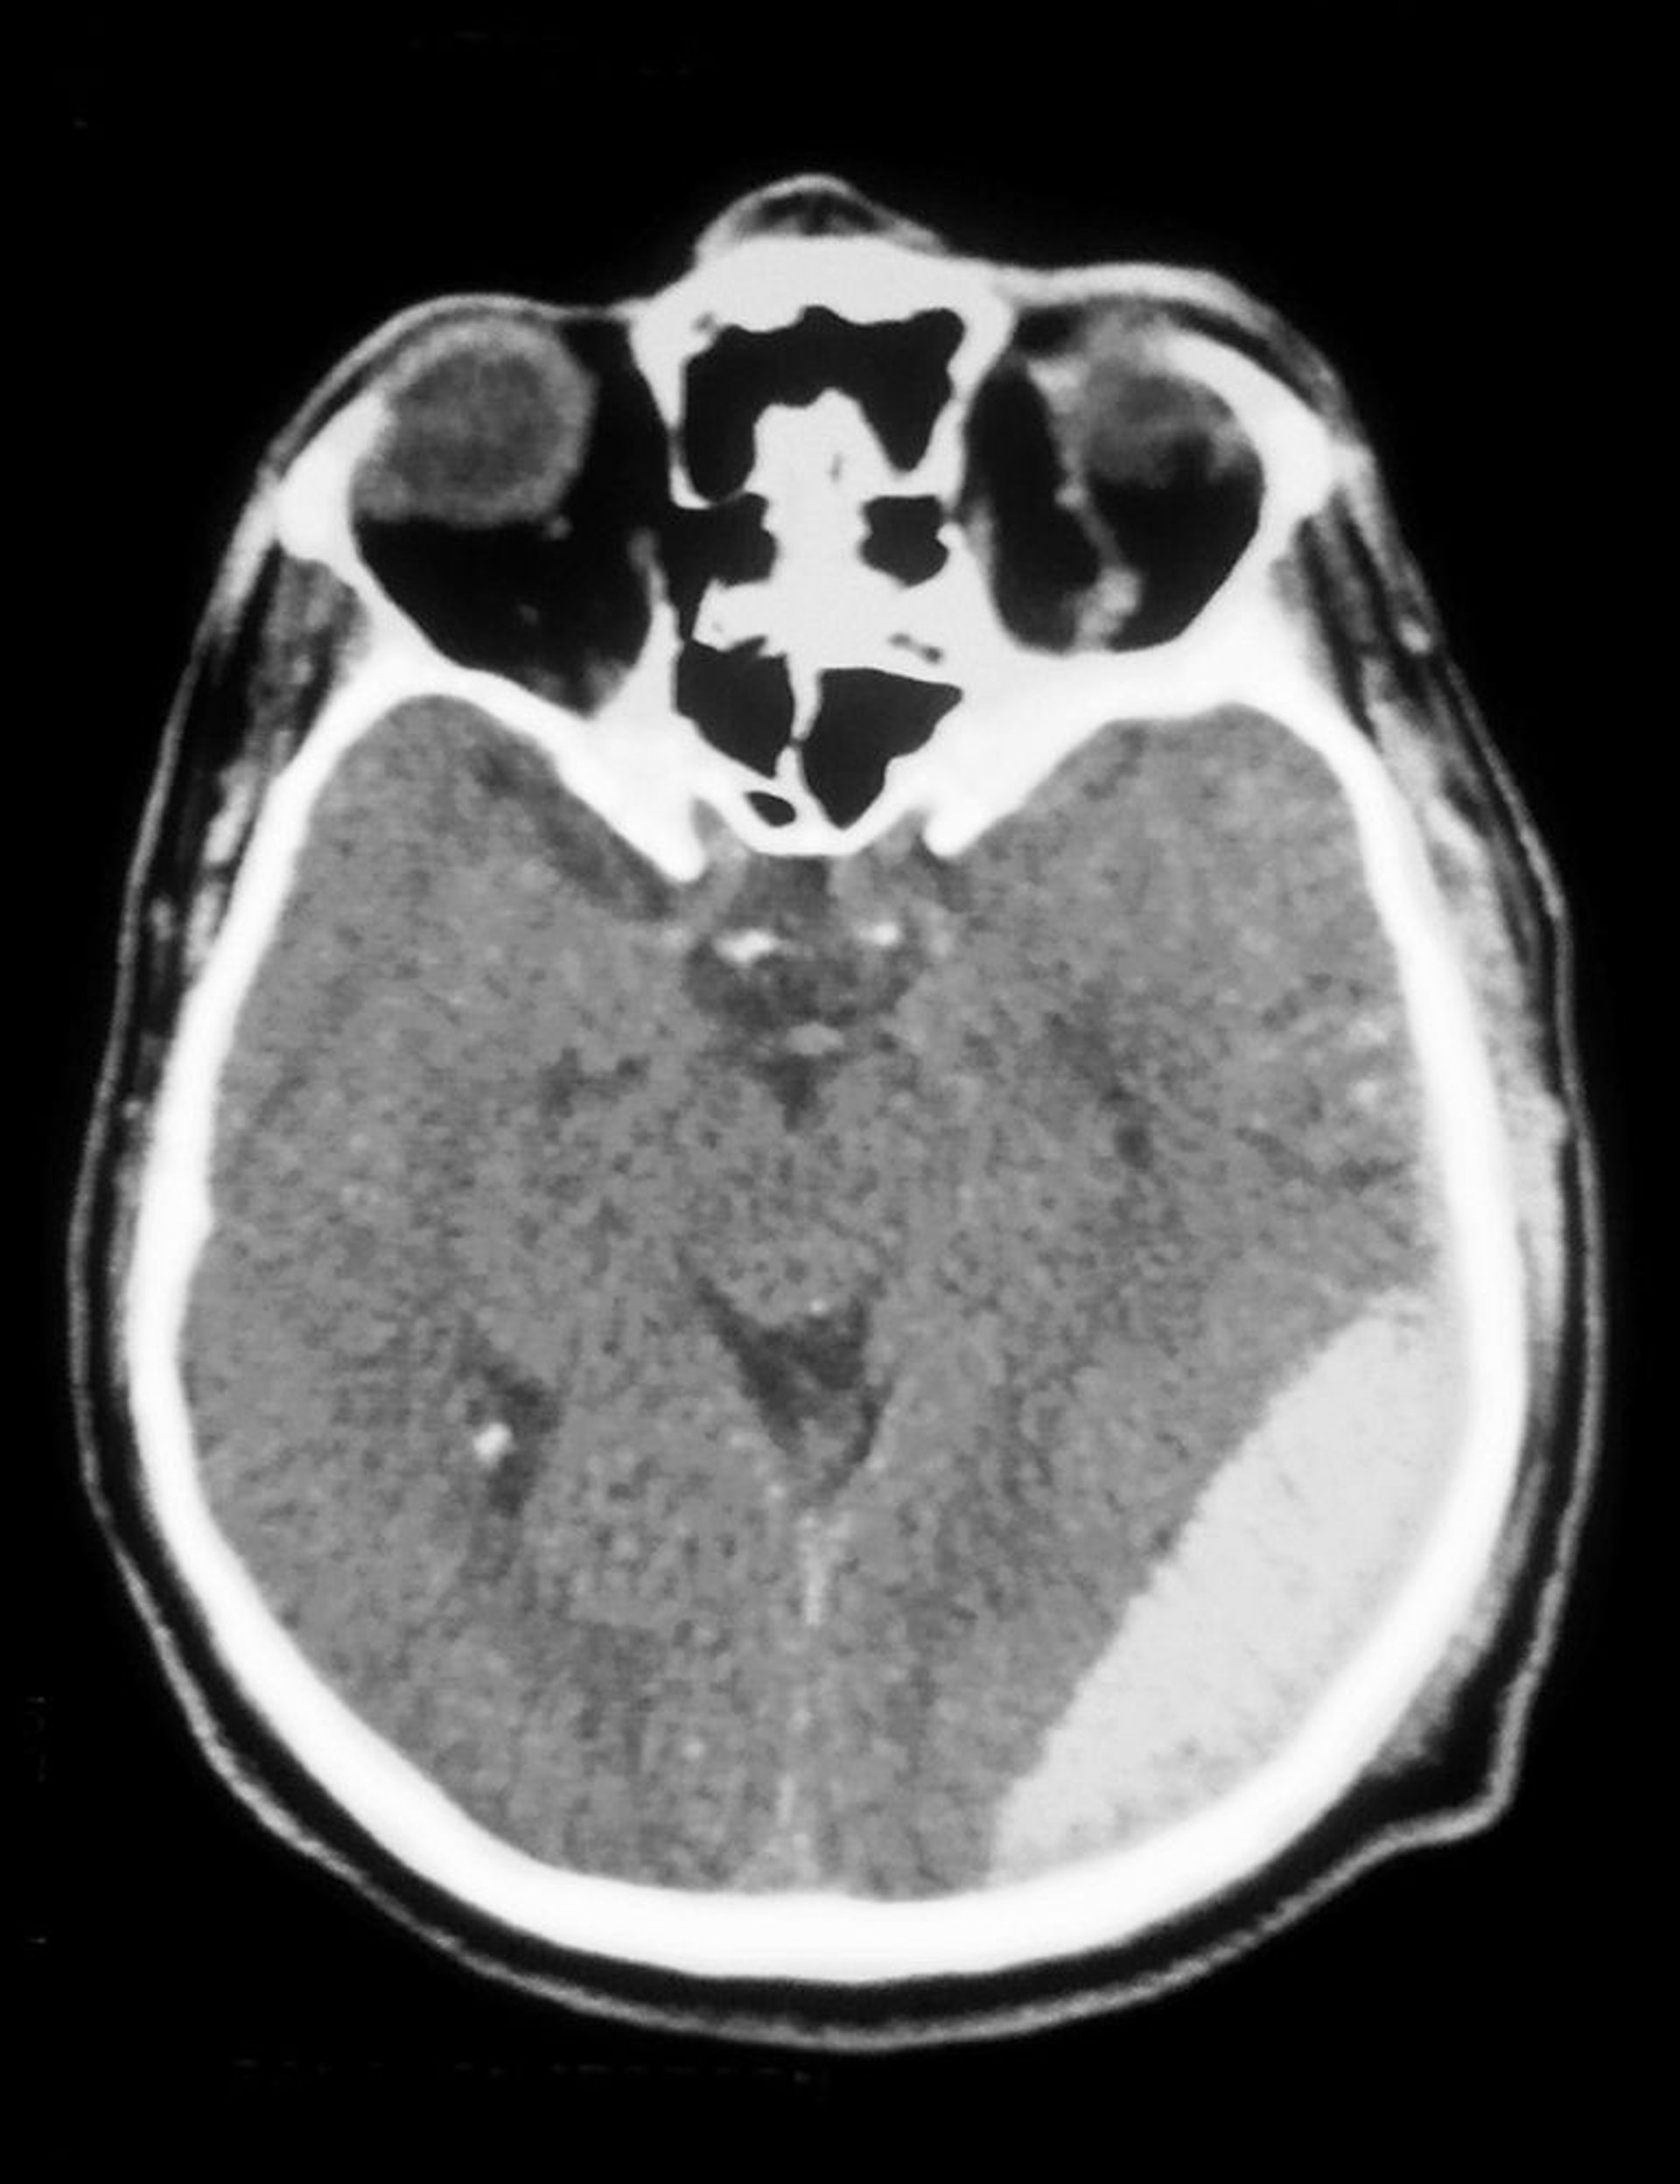

硬膜外血腫

CT上で硬膜外血腫(右下の陰影)を認める。

Cavallini James/BSIP/SCIENCE PHOTO LIBRARY